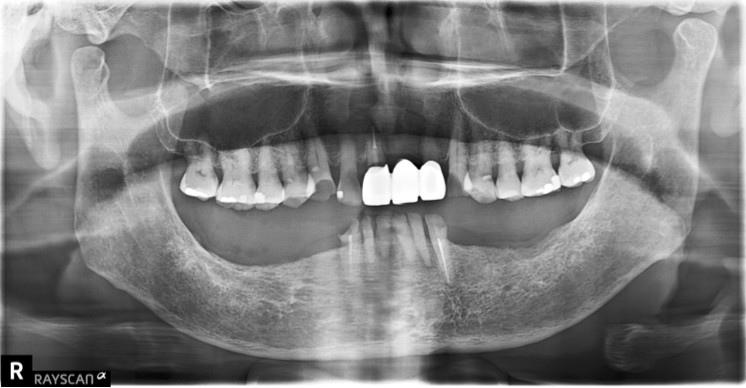

【全口重建:下顎無後牙支撐,上顎前牙假牙做了四年以後破損】 【治療醫師:林農翔 醫師】 林先生四年前完成的上顎前牙假牙來診時已經破損,下顎僅剩的六顆牙齒可以說是 …